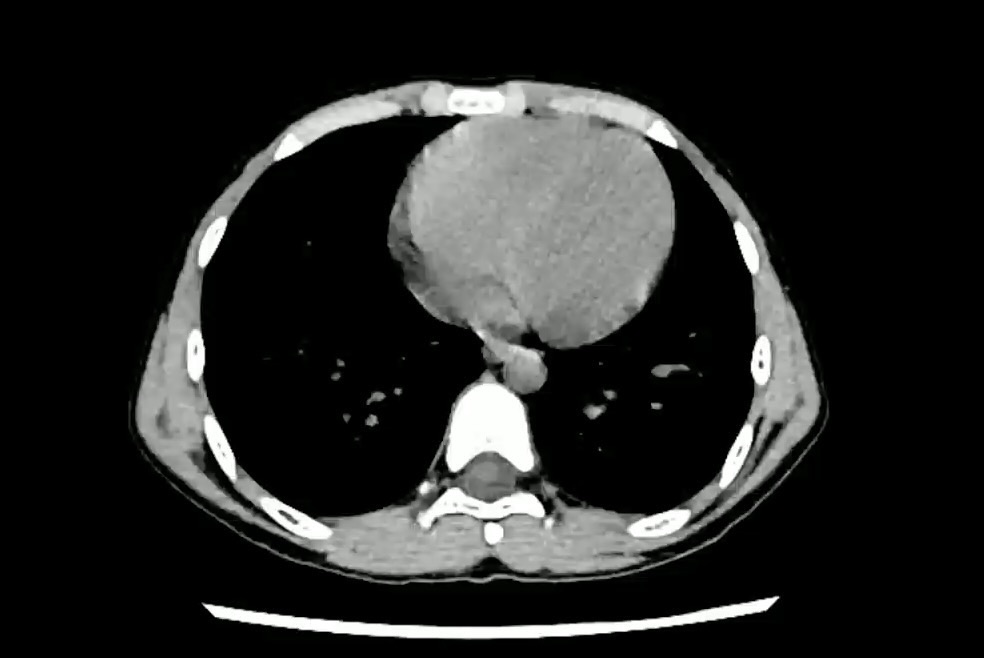

【腹盆】患者1小时前从高约2米处摔下,腹部硌到小区锻炼用的单杠上了。男,10岁。

【患者信息】:男,10岁。

【主诉】:患者1小时前从高约2米处摔下,腹部硌到小区锻炼用的单杠上了,伤后自觉腹痛。无恶心、呕吐。